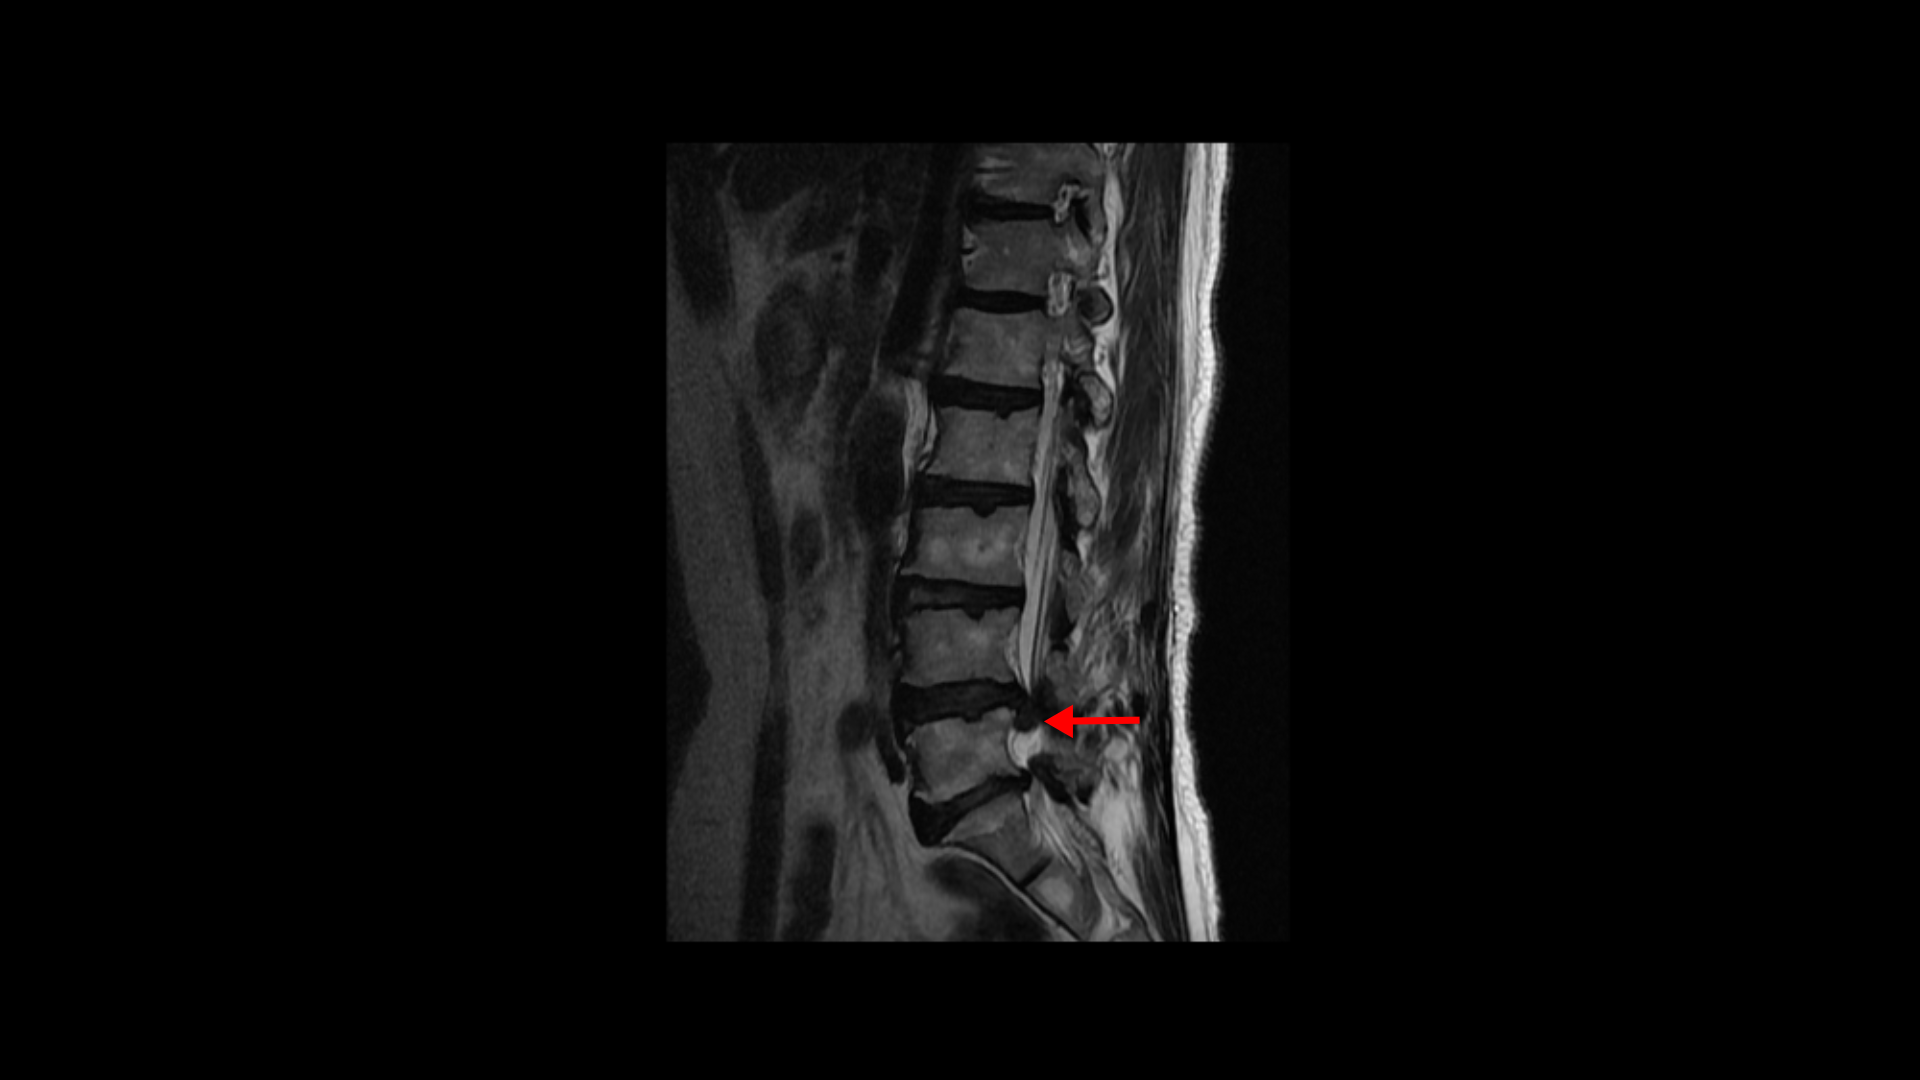

이분은 약 4달 전에 디스크가 갑자기 파열됩니다. MRI를 보면 4번 5번 디스크가 터져서 밀려나온 수핵이 아래로 흘러내려 있습니다.

이 파열된 디스크로 인해 극심한 엉치 통증과 다리의 방사통이 발생합니다.

3회의 신경 주사도 전혀 듣지 않았고 수술 외에 어떠한 방법도 없다는 의사 소견에 수술 동의서까지 서명한 상태에서 지인분의 강력한 추천으로 디스크 파열의 비수술 재활치료를 위해 모커리를 내원하셨습니다.